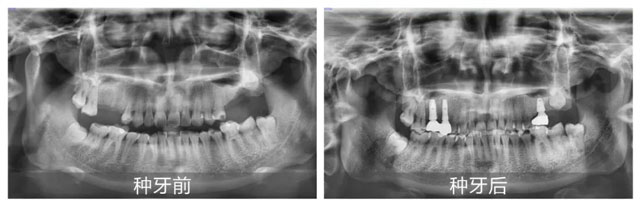

新桥口腔成都玉双院区的口腔修复医生代艳,为田女士进行了全面且细致的面诊。在获取田女士详细的体检报告,并进行全面综合评估后,代艳医疗团队确认其身体状况适合接受手术,于是果断定制了多颗种植修复方案。当天,田女士便顺利完成了手术。 田女士回忆治疗过程时说道:“这里的医护人员太贴心了!治疗结束后,他们有定期回访,仔细叮嘱治疗后的各类注意事项,时刻关注我的恢复情况,让我心里特别踏实。”

田女士种植手术当天,陪她一同前来的儿子许先生,被这里的服务吸引。在母亲看诊间隙,许先生咨询了正畸相关问题。新桥口腔成都玉双院区的口腔正畸医生王利,为他进行了详细面诊。结合全景片、CBCT、口扫检查结果,王医生判断其牙列不齐,考虑到成人正畸,矫正时间会稍长一些。最终,许先生决定接受矫正治疗。